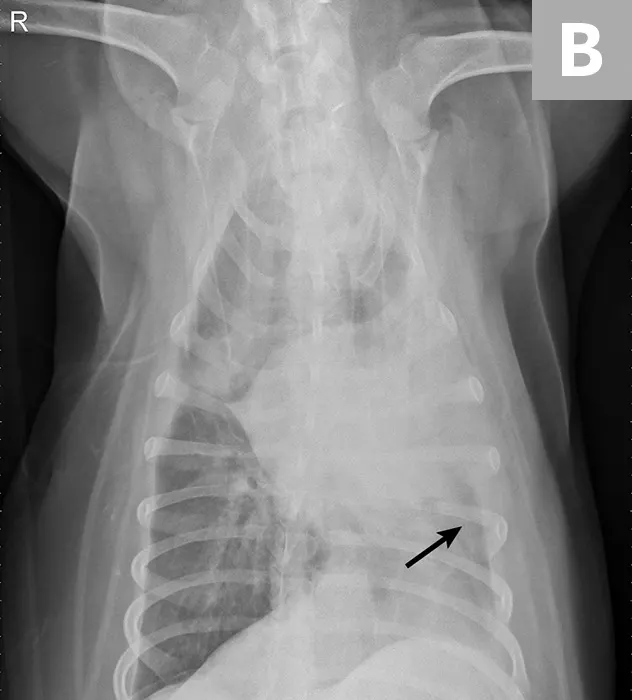

Right lateral thoracic radiographs revealed a large amount of fluid/soft tissue opacity obscuring the cardiac silhouette. Ventrodorsal radiographs showed increased soft tissue opacity in the left hemithorax, primarily in the cranial and middle lung fields. A mild interstitial pattern, a pleural fissure line, and border effacement of the heart were noted in the left hemithorax (Figure 1).

FIGURE 1A

Right lateral (A) and ventrodorsal (B) thoracic radiographs obtained prior to thoracocentesis demonstrating a mild interstitial pattern, moderate pleural effusion, soft tissue opacity in the left cranial and middle lung field, border effacement of the heart, and a pleural fissure line (arrows)